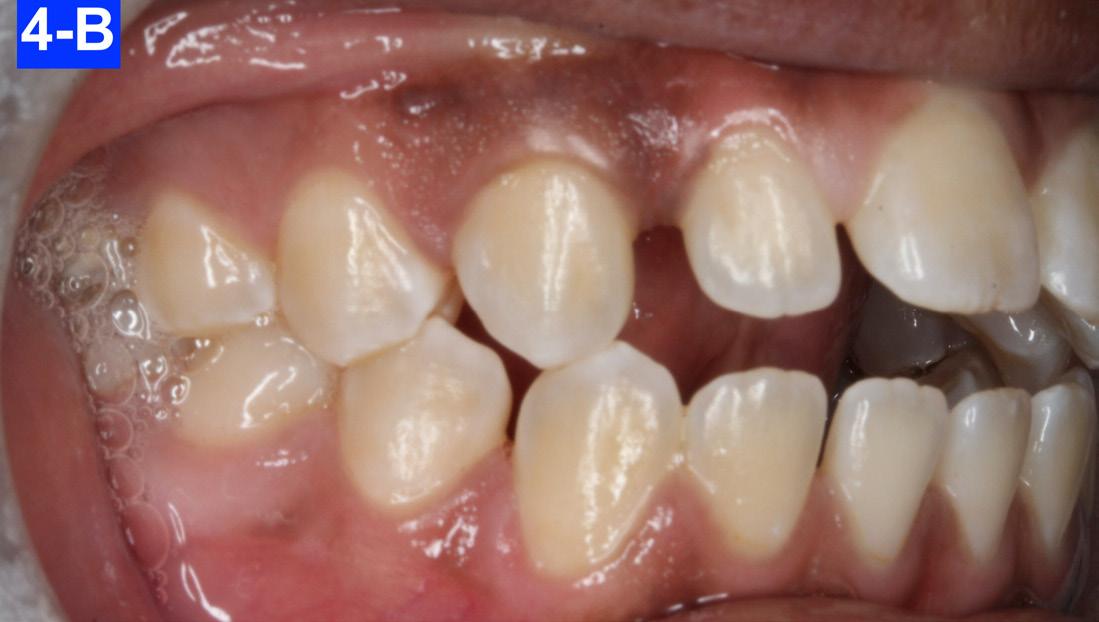

Clinical Micro-esthetic appraisal revealed a full Angle Class I molar and cuspid relationship. The arches were wide, there was generalized spacing in the anterior region. The patient had 2.0 mm overjet and -3.0 mm overbite. Maxillary lateral incisors appeared to be microdonts (Figures 4-A, B, C, D).

Fig. 4-C: Pre-treatment, left lateral view